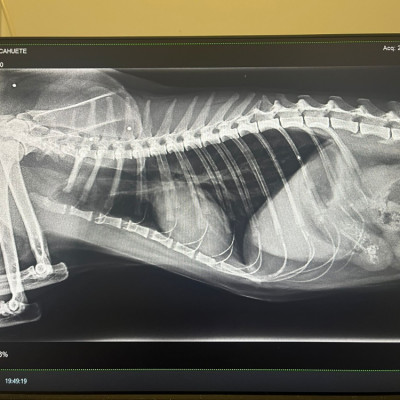

Lo rescatamos desde Francia, y, al llegar aquí, nos encontramos con este panorama desolador para él:  una auténtica barbaridad de perdigones en el cuerpo y una cardiopatía ❤️‍🩹 Las imágenes hablan por sí solas...